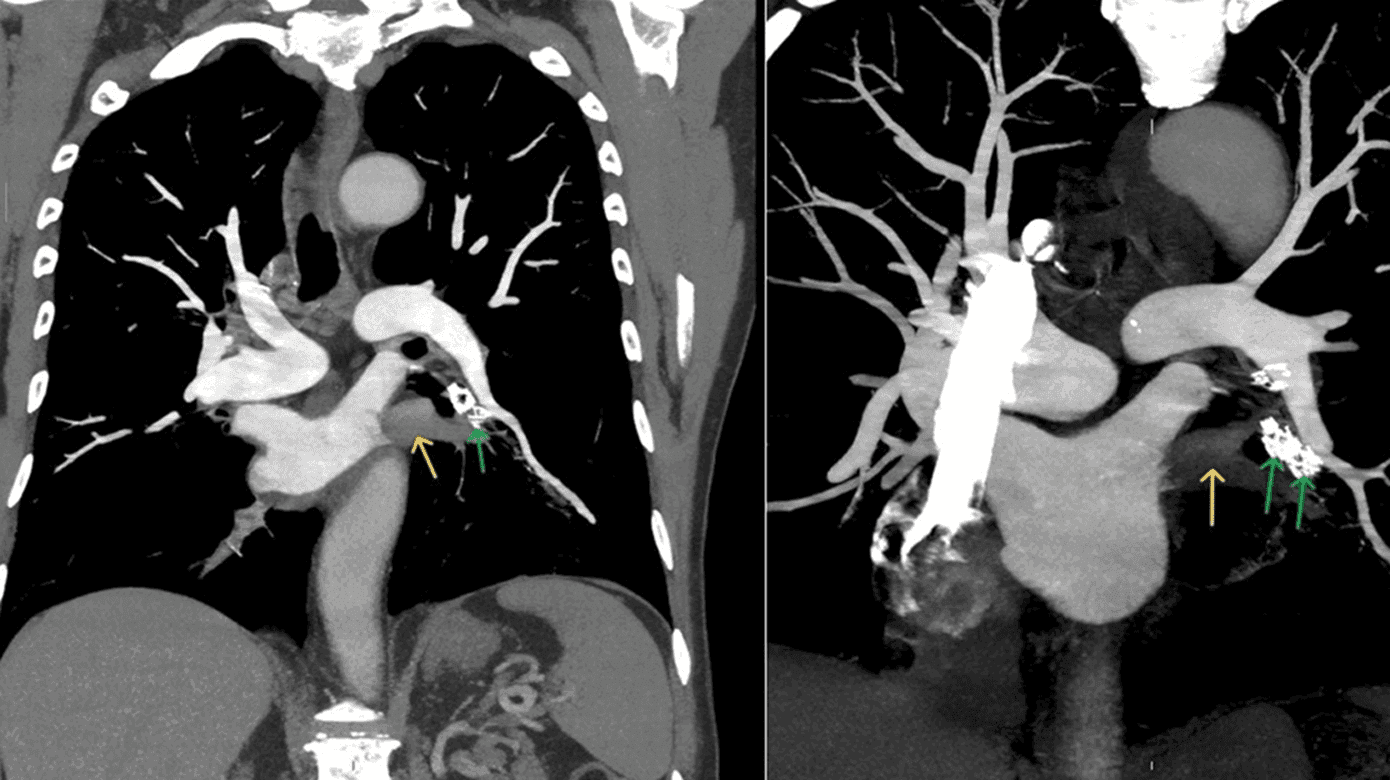

En 73-årig mand, diagnosticeret med svær lungeemfysem, der foruden inhalationsmedicin havde fået indsat fire endobronkiale ventiler i venstre lunges underlap, indsat bronkoskopisk ultimo juni 2024, blev indlagt ultimo september 2024 på fælles akutmodtagelsen grundet pludselig forværring af ellers kendt dyspnø. Ingen hoste eller produktivt opspyt. I ambulancen fik patienten bronkodilaterende inhalationsmedicin uden den store effekt. Ved ankomst havde patienten takykardi, marginalt forhøjede D-dimer på 1,17 mg/l fibrinogenækvivalente enheder (FEU) og en Wells score på 1,5 grundet takykardien. På mistanke om lungeemboli blev der foretaget CT-angiografi af thorax. Denne skanning viste noget overraskende trombemasse i de venstresidige kaudale pulmonale vener, beliggende i relation til de fire endobronkiale ventiler, strækkende ind i venstre atrium (Figur 1).

En efterfølgende TTE viste, at der var tegn til udfyldning samt fravær af flow svarende til venstre inferior pulmonalvene. Patienten havde forud for CT-angiografi af thorax fået dalteparin svarende til 200IE/kg og blev senere omlagt til direkte oral antikoagulantia, der blev planlagt som livslang behandling.

Der er ikke tidligere beskrevet direkte sammenhæng mellem endobronkiale ventiler og udviklingen af PVT. I et nyligt studie fra juli 2024 fandt man, at 17% af PVT skyldtes ydre kompression af en pulmonalvene førende til trombosedannelse. Den hyppigste årsag til kompression af pulmonalvenerne var tumormasse, sjældent fandtes mediastenal fibrose og lymfadenopati i hilus som årsag til dette [2]. Som vist på CT (Figur 1) er de endobronkiale ventiler lokaliseret nært den venstre kaudale pulmonalvene, hvorfor en sammenhæng virker indlysende, uden der foreligger sikker evidens herfor.